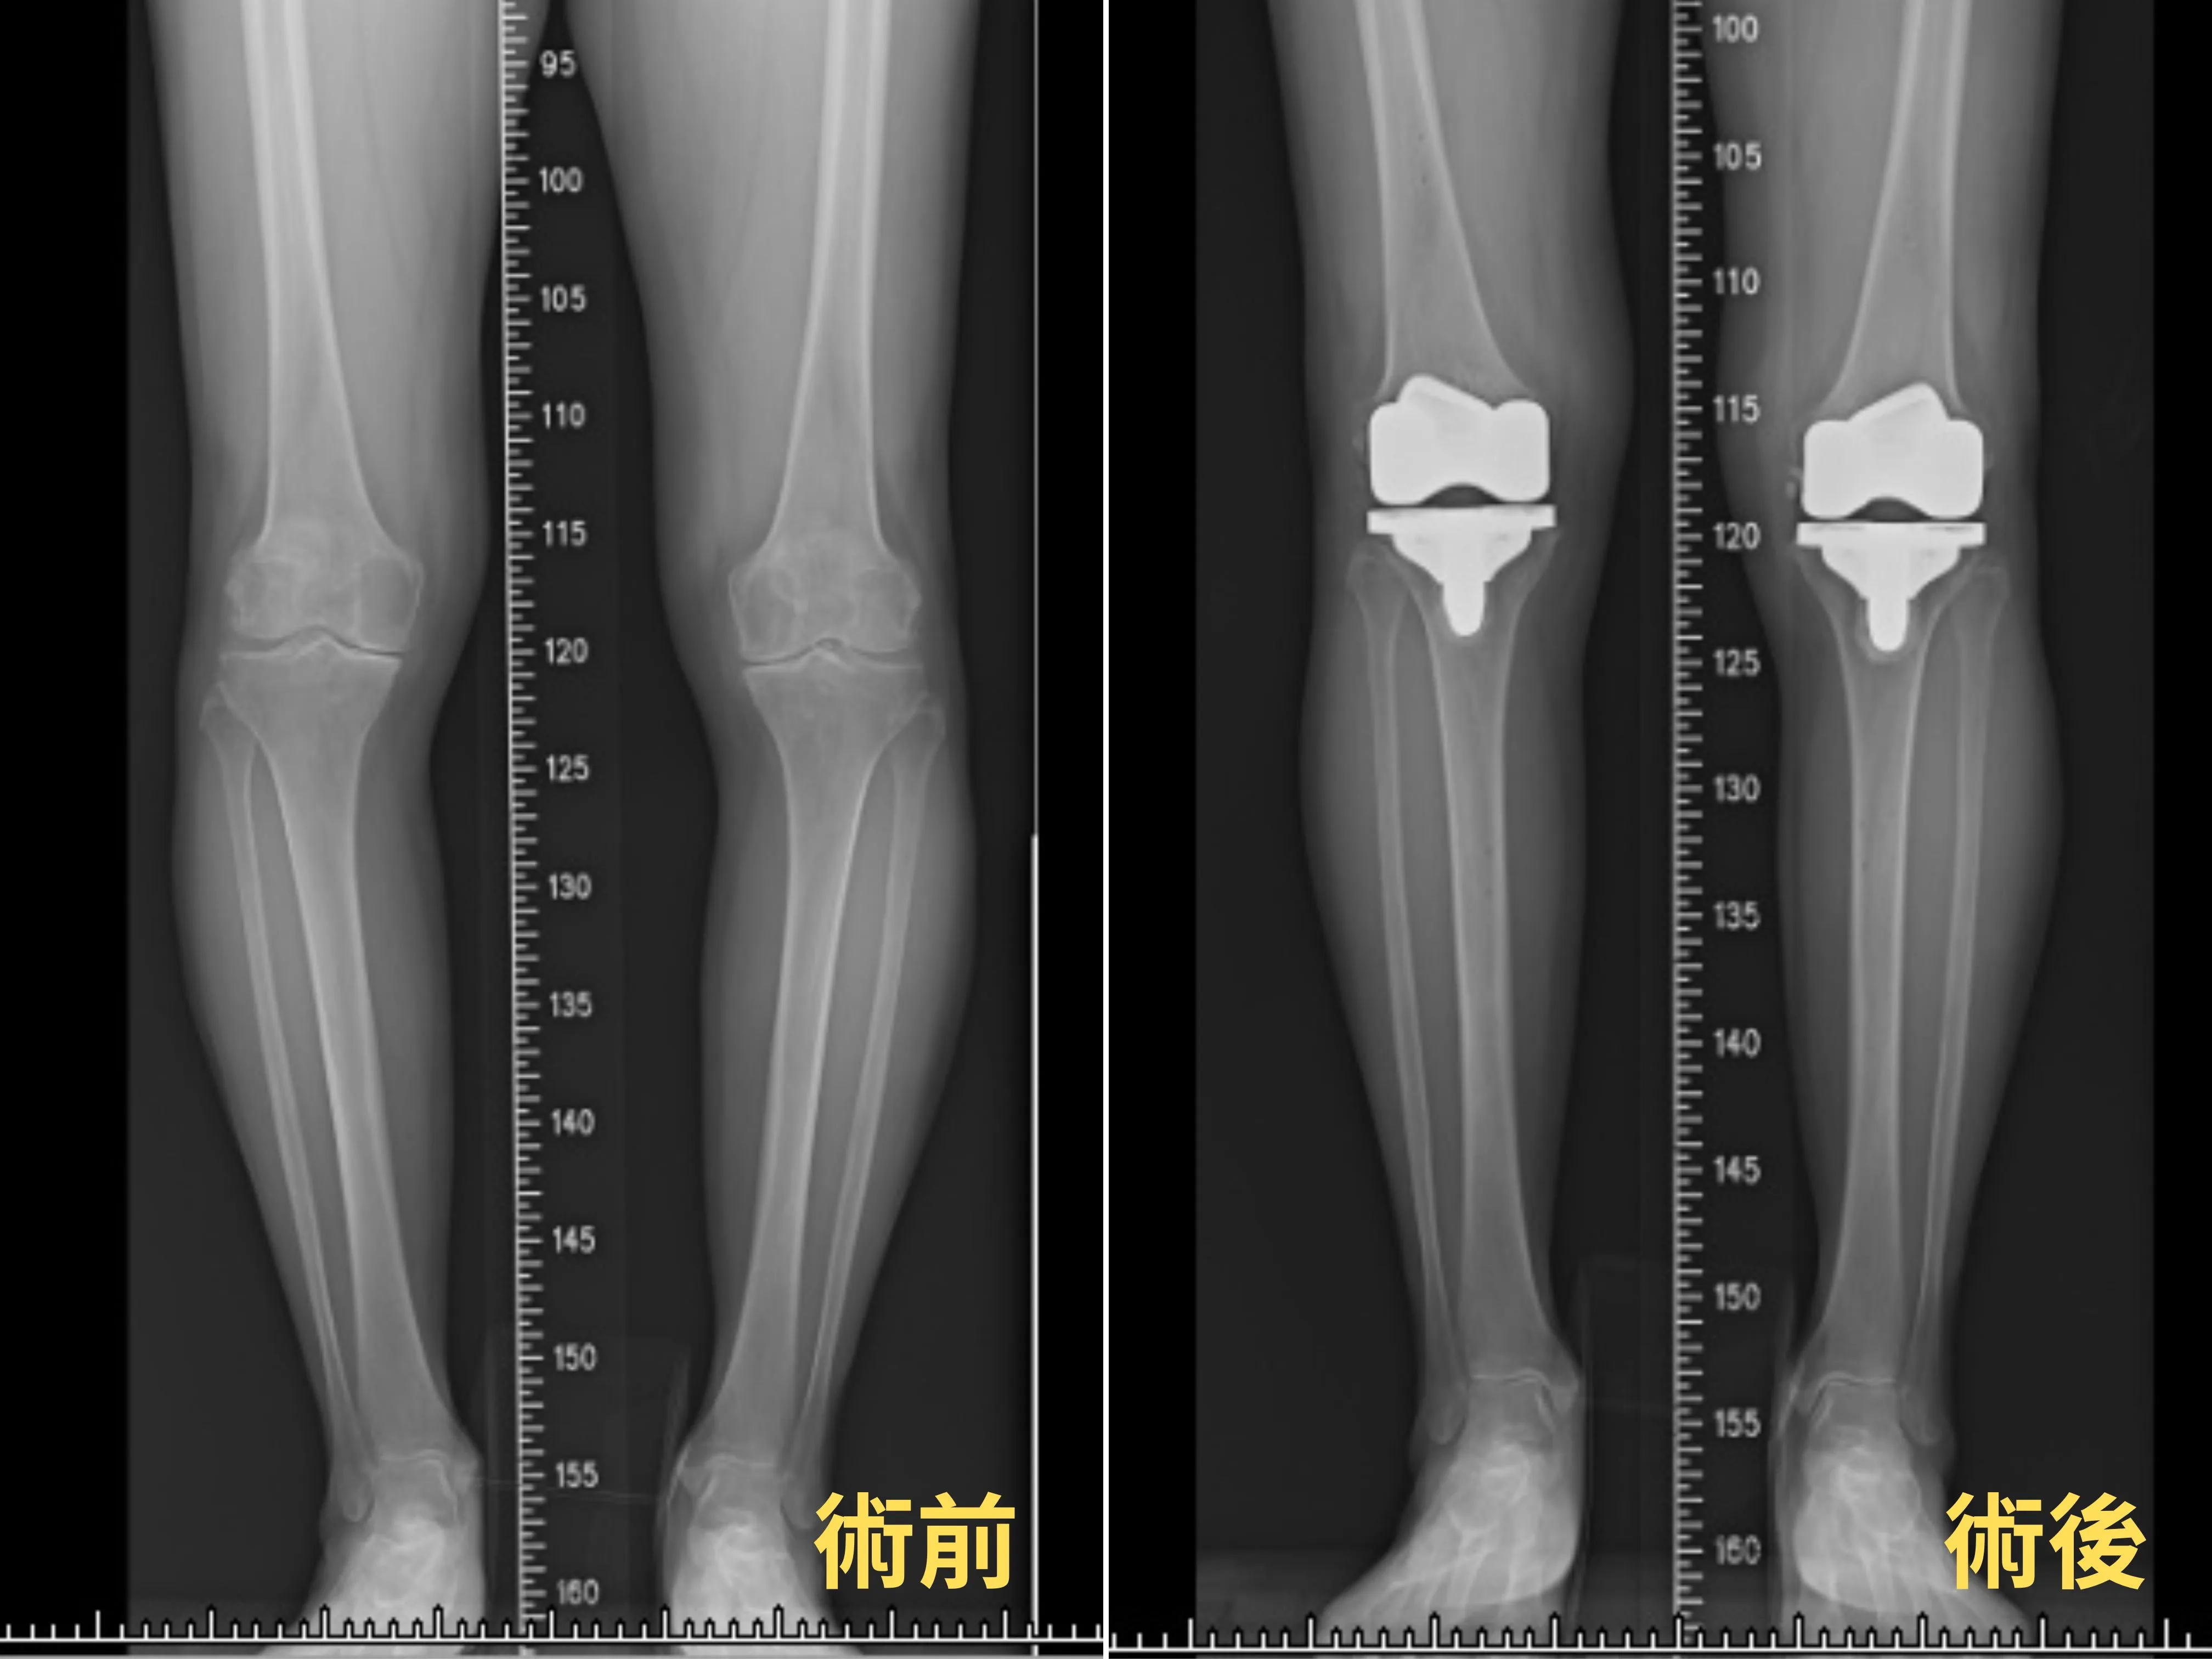

陳女士術前、術後X光片,Mako®機器手臂的量身定制功能使人工關節完美契合患者的腳型。

楊志鴻醫師表示,精準定位是膝關節置換手術成功的關鍵,而這正是Mako®機器手臂的優勢所在。它能根據患者的膝關節角度及下肢軸線,精確設計出最適合的人工關節尺寸及擺放位置。與傳統手術相比,Mako®機器手臂不僅能縮小手術傷口,還能保留健康的骨本和韌帶組織,使患者術後恢復更快。

楊志鴻醫師指出,Mako®機器手臂的量身定制功能使人工關節能完美契合患者的腳型,讓術後的活動更加自然。他呼籲民眾,如果有關節疼痛的情況,應該盡早就醫,找出最適合自己的治療方式,從而擺脫膝關節退化的困擾,重拾生活品質。